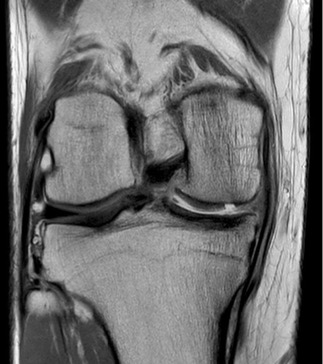

- Das Kernspintomogramm ist stets Teil unserer Analyse. Hier finden sich sektorale Knorpeldefekte innenseitig am rechten Knie sowohl am Oberschenkel als auch am Schienbeinkopf. Die seitliche Aufnahme (rechts) zeigt eindrucksvoll diie Knochenmarködeme an Femur und Tibia (Aufhellungen) als Ausdruck der Überlastung.